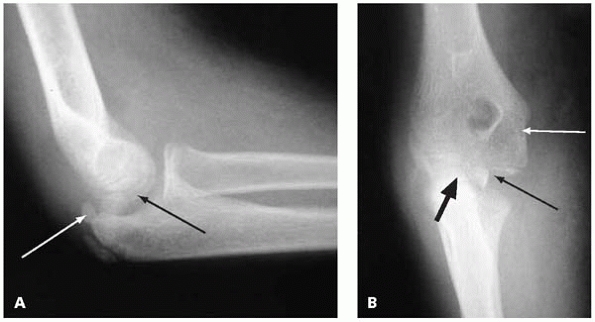

![]() |

|

▪ FIGURE 6-13 A: Lateral view of elbow demonstrating an incarcerated medial epicondyle (black arrow) following spontaneous reduction of a dislocated elbow. Note that the olecranon apophysis is ossified (white arrow), suggesting the child is skeletally mature enough that the medial epicondyle should be ossified and visible on the AP view. B: Anteroposterior view of same elbow. Note that the trochlea is beginning to ossify (thin black arrow), suggesting the medial epicondyle should be visible, but is absent from its anatomic position (white arrow). The mystery is solved by identifying the medial epicondyle in the joint (thick black arrow).

fracture associated with an elbow dislocation that has become

incarcerated in the joint, which occurs in about 15% of cases. It may

be quite difficult to see the fracture fragment in the joint, but one

should become suspicious if the ossification center for the medial

epicondyle is not appreciated after the ossification centers for the

trochlea and/or olecranon is present. Remember, the order of

ossification (see Fig. 5-1) is capitellum,

radial head and/or medial epicondyle, trochlea and/or olecranon, and

If the trochlea and olecranon centers are present (which ossify at 8 to

9 years old), but the medial epicondyle (ossifies at 4 to 5 years old)

is not in its proper place, be suspicious of an incarcerated medial

epicondyle fracture and look in the joint (Fig. 6-13).